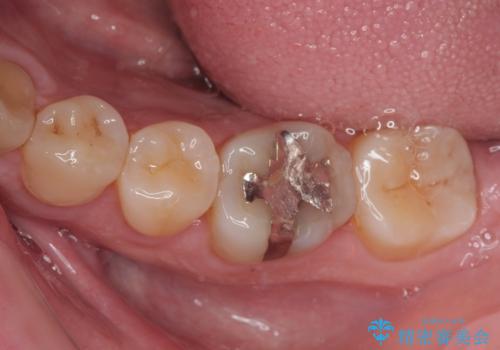

「他の歯も、せっかくなら精度の良いものに替えておきたい」とのご希望があり、

上顎左側第一大臼歯

下顎左側第一大臼歯

に入っていた保険診療の銀歯(メタルインレー)を、精度の良いゴールドインレーへやり替えを行いました。